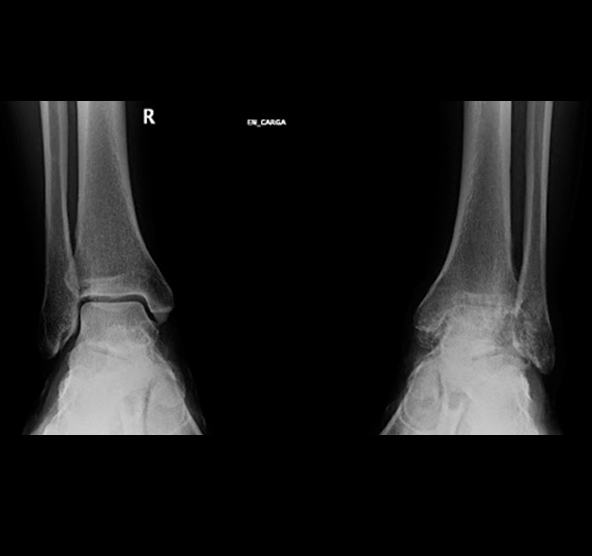

ARTROSIS DE TOBILLO

La artrosis de tobillo es el desgaste progresivo de las superficies articulares que conforman el tobillo, la cara articular de la tibia, la del astrágalo y la del peroné.